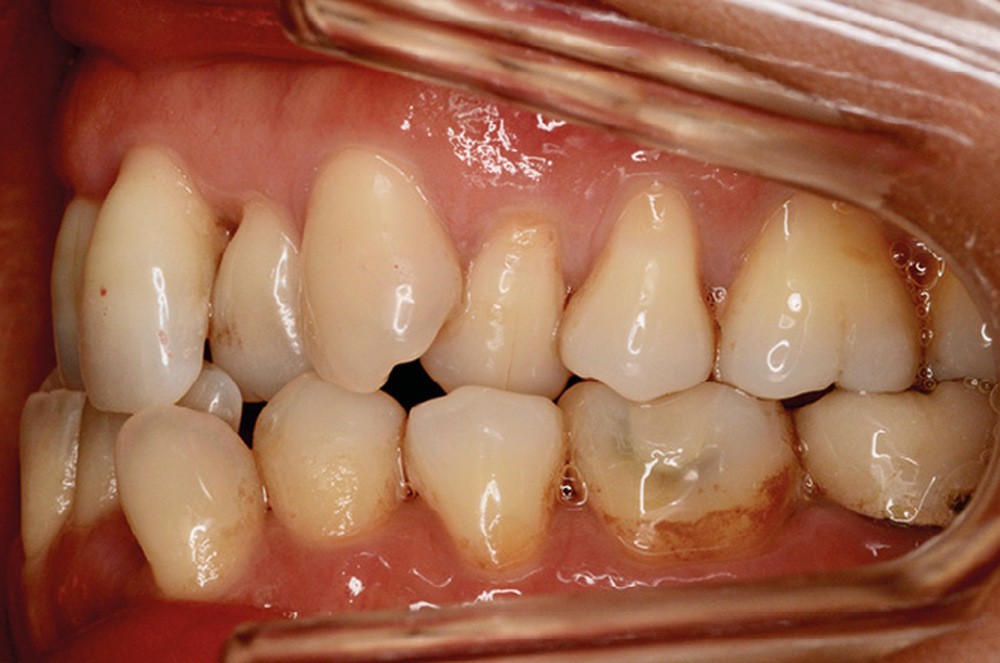

Sur le plan dentaire, la patiente est en classe III droite et gauche, canine et molaire de 6 mm, avec une occlusion inversée antérieure localisée à 11, 12 et 22. Elle présente une dysharmonie dents-arcades sévère, une agénésie d’une incisive mandibulaire est à signaler, et les troisièmes molaires ont été extraites à l’âge de 21 ans.

Au niveau fonctionnel, on note un bruxisme statique avec contact permanent entre les dents maxillaires et mandibulaires. La patiente présente des prématurités en relation centrée sur les incisives, le guidage en propulsion est perturbé et des interférences multiples sont retrouvées en latéralités droite et gauche.